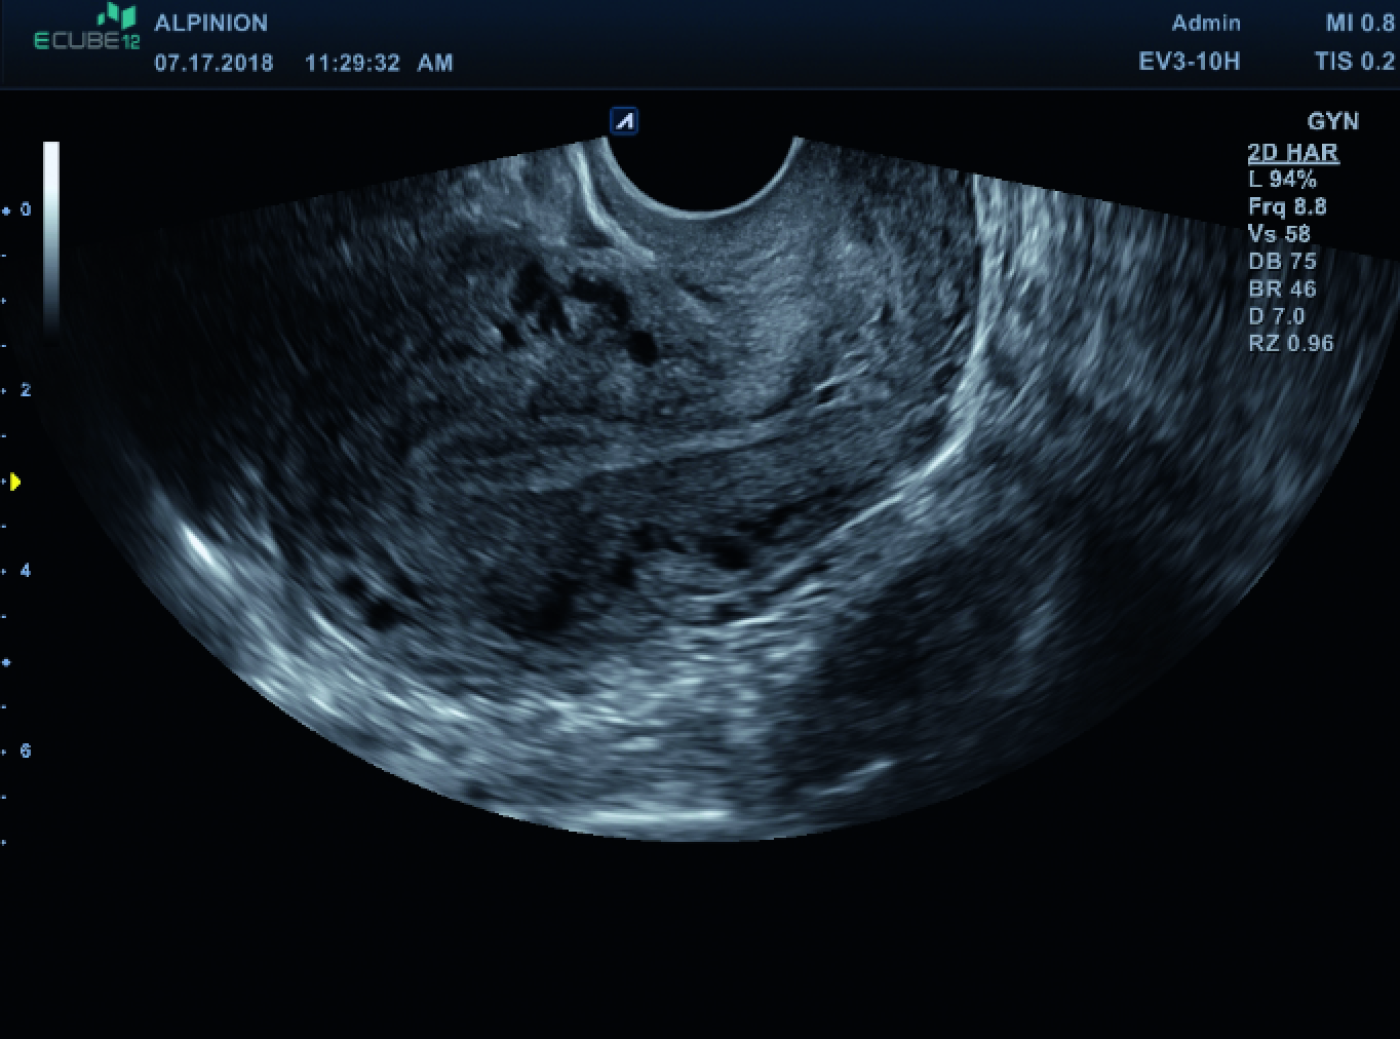

Gynäkologische

Ultraschalldiagnostik

mit Präzision & Komfort

Moderne Frauenheilkunde stellt höchste Anforderungen an Bildqualität, Bedienkomfort und Vielseitigkeit. ALPINION unterstützt Gynäkologinnen und Gynäkologen mit leistungsstarker Ultraschalltechnologie, die sowohl im Praxisalltag als auch im klinischen Umfeld überzeugt. Unsere Systeme liefern hochauflösende Bilder bei transabdominaler und transvaginaler Sonografie – für eine sichere, schnelle und präzise Diagnostik in allen Phasen der Frauengesundheit.